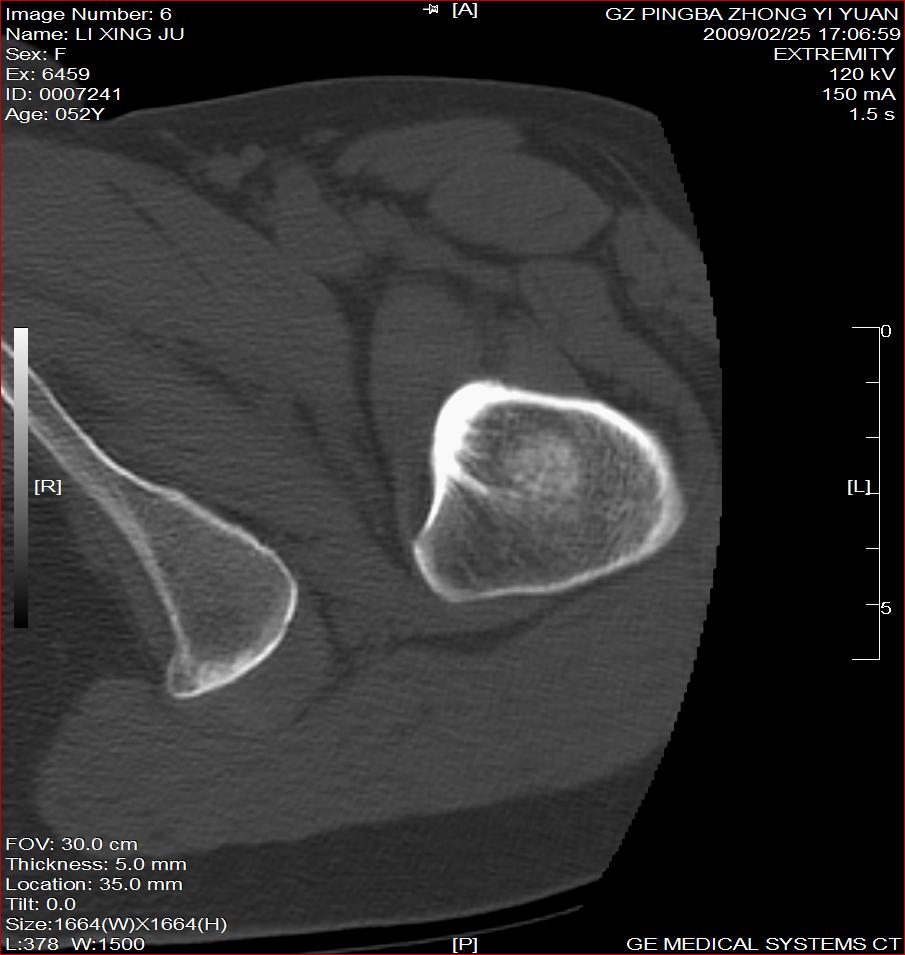

标题: CT18521:左大腿疼痛不适1+月 [打印本页]

标题: CT18521:左大腿疼痛不适1+月

考虑-----股骨骨化性纤维瘤可能性大,不除外---局限性骨纤

考虑:左股骨骨化性纤维瘤

考虑:骨纤或骨梗可能性大

骨梗塞

考虑:左股骨骨化性纤维瘤。